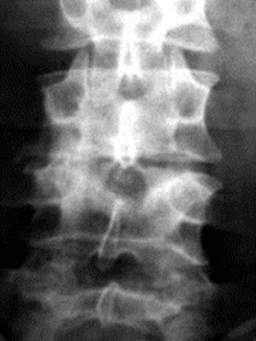

Діагностика КСТ завжди повинна починатися з оглядової рентгенографії. Рентгенографічний метод зберігає базове значення, на його основі розроблені сучасні уявлення про захворювання скелету, що використовуються і при аналізі результатів КТ, МРТ, остеосцинтіграфії та ін. Ніякий інший метод не дає більш виразного зображення кісткових елементів опорно-рухового апарату. При вірному технічному використанні рентгенографія і рентгенотомографія досить інформативні в характеристиці кісткової структури, масштабів руйнування і характеру обмеження його, загального структурного фону, змін в паравертебральних (параартикулярних) тканинах (рис. 1). Оглядові знімки у двох проекціях повинні бути прицільними, центрованими на рівень ураження і діафрагмованими.

Рис. 1. Туберкульозний спондиліт L3-L4 (прямий та боковий оглядовий знімок). Візуалізується осередковий контактний характер кісткової деструкції, нерівномірне звуження міжхребцевого простору.